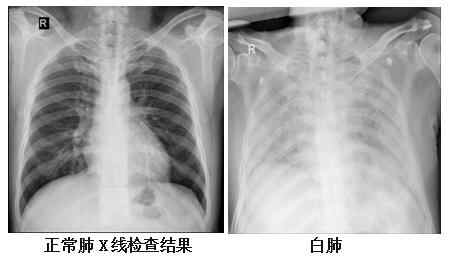

复旦大学附属华山医院感染科副主任医师张继明介绍,正常情况下,肺部主要是由充满了空气的肺泡组成,进行CT或者是X线检查时,射线可以很容易地穿透肺泡,在影像学上显示为黑色区域;当肺部受到病原体感染、临床上表现为重型肺炎时,患者肺泡里会出现炎症、渗出或实变时,射线不容易穿透病变区域,在影像学就出现了白色的区域。当白色区域面积达到了70%-80%时,临床上俗称其为“白肺”。

事实上,“白肺”患者,其肺组织肉眼下看并不是白色的。

他表示,“白肺”是肺组织炎症渗出、肺实变所导致的一种影像学表现,“白肺”患者常常病情较为严重,预后较差。